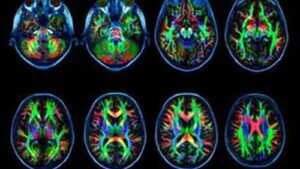

Tecniche di risonanza magnetica hanno permesso di scoprire che cosa avviene nel nostro cervello quando effettuiamo una simulazione per immaginare...